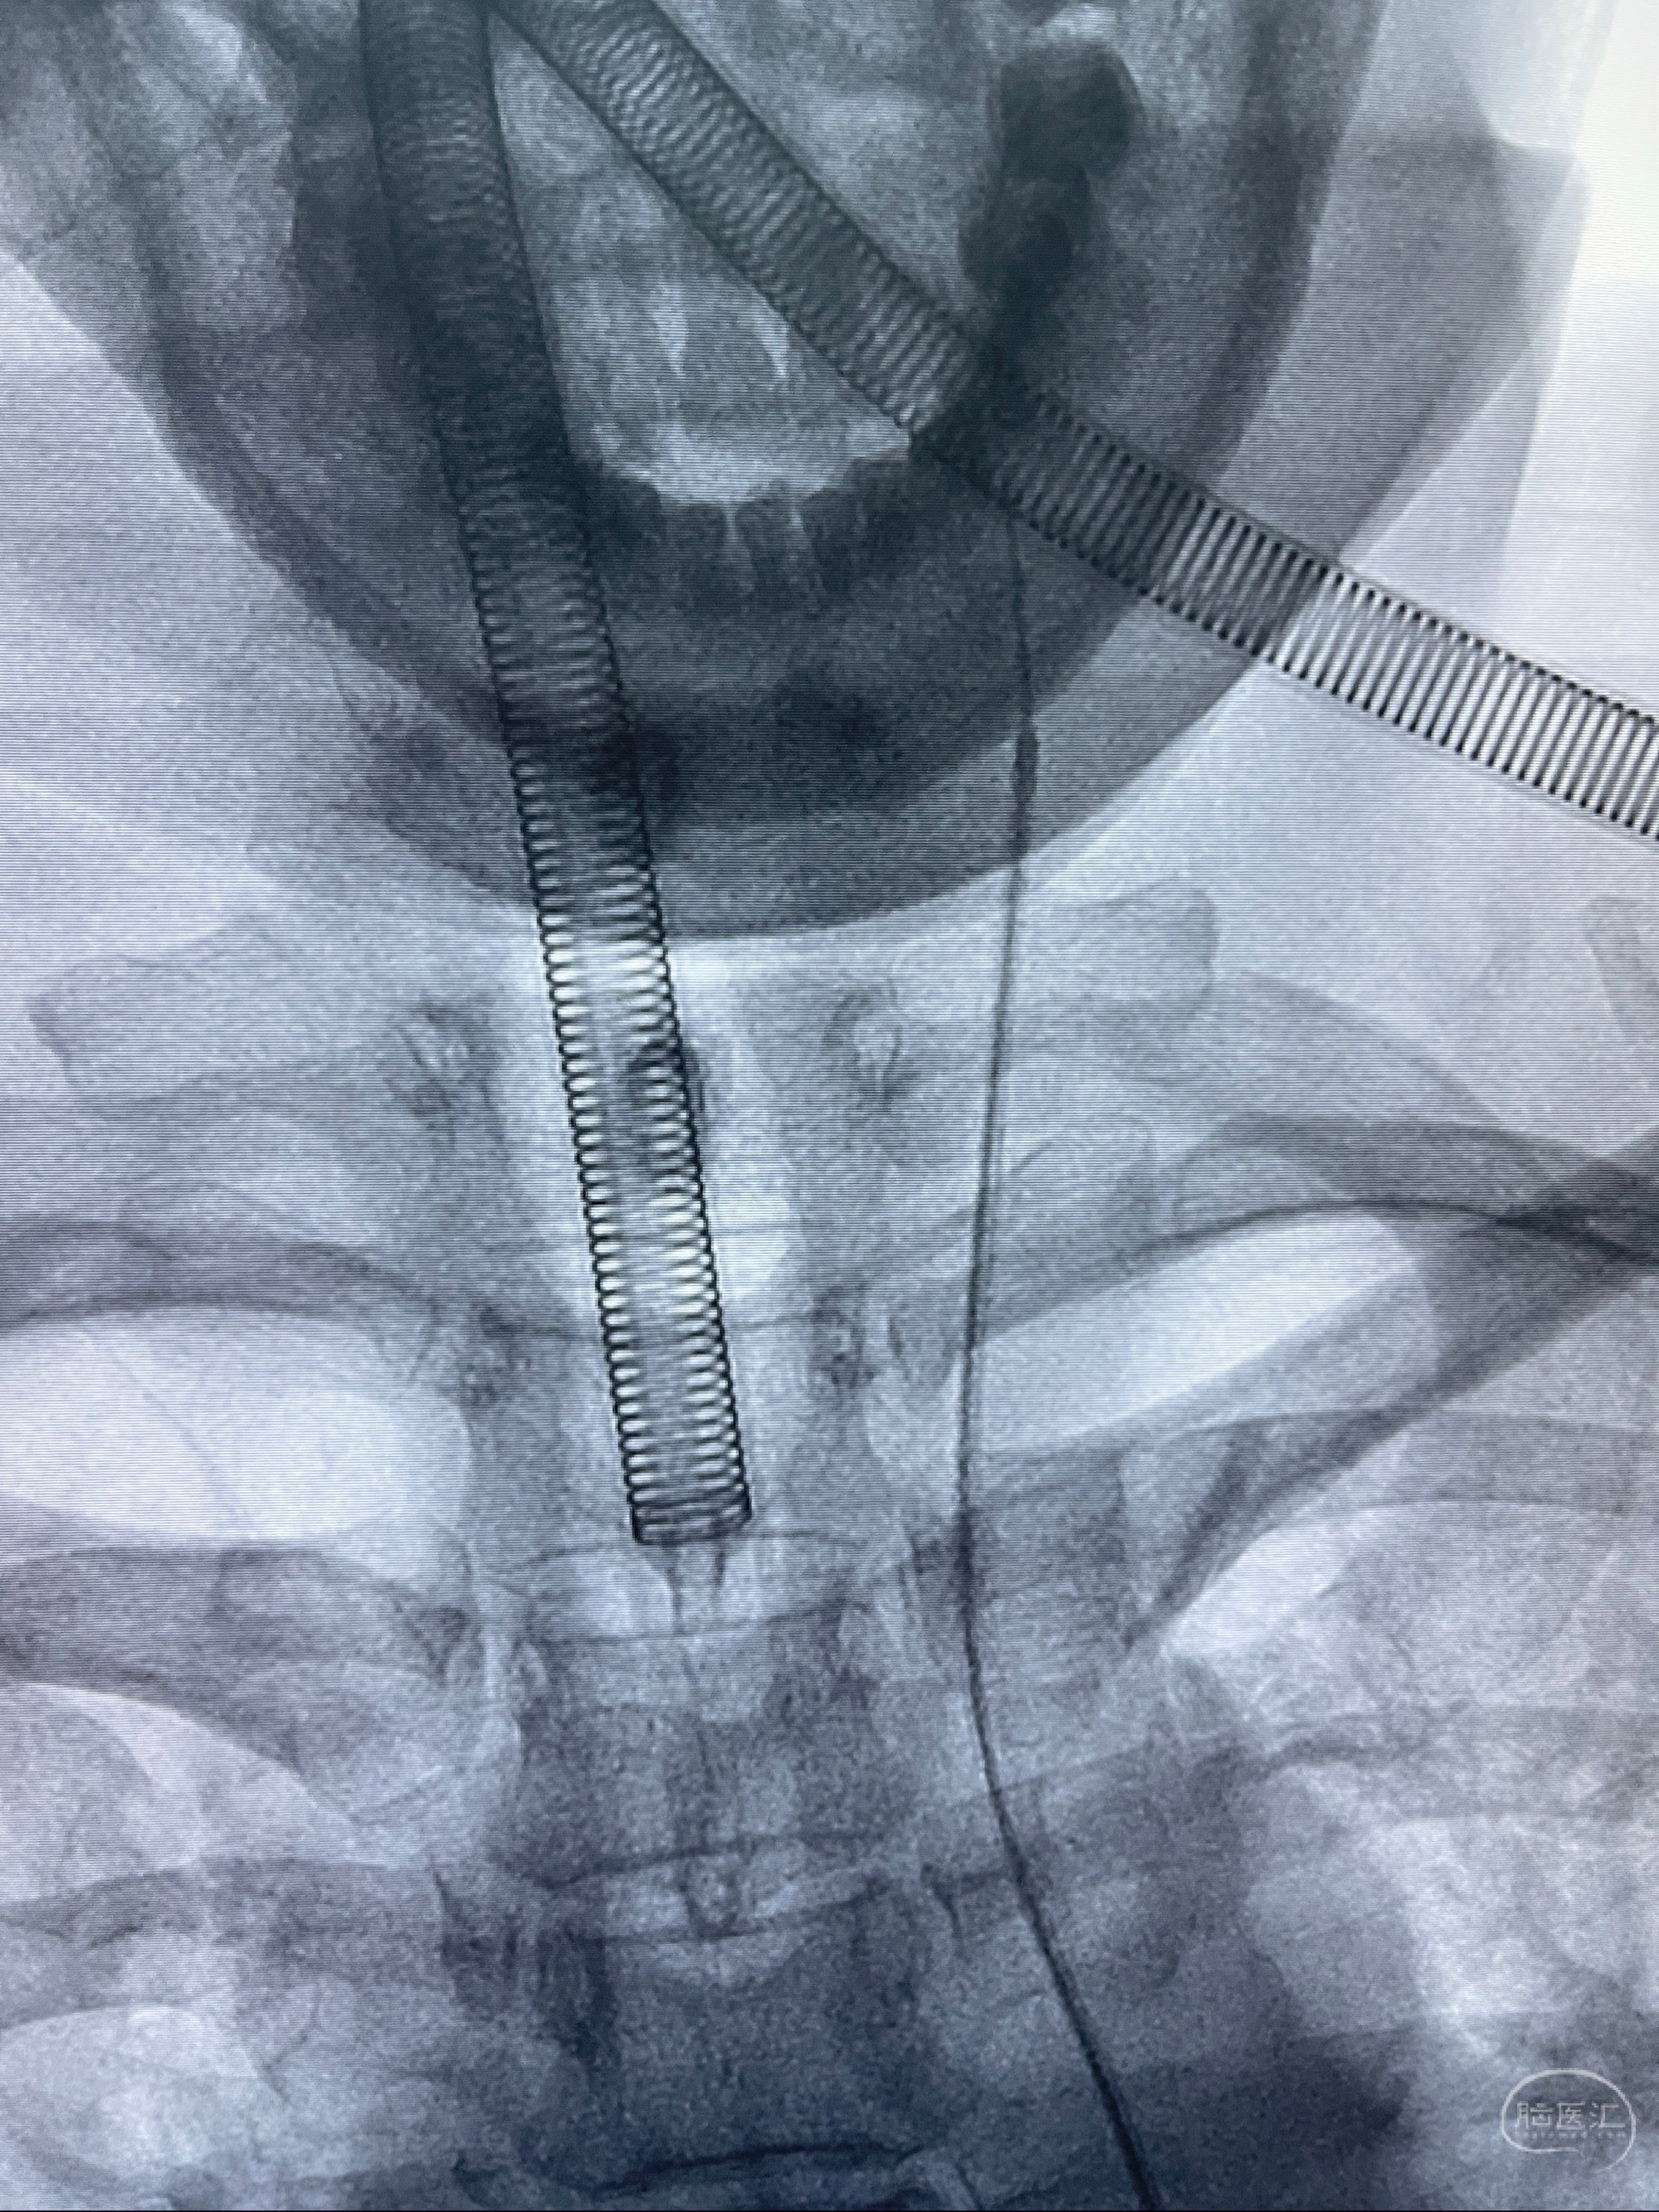

2023-08-01全麻下行双侧颈眼动脉瘤支架辅助栓塞

- pipeling4.5-20mm

- pipeline 4.0-20mm

手术顺利,麻醉苏醒佳,遵嘱动作

术后即刻CT